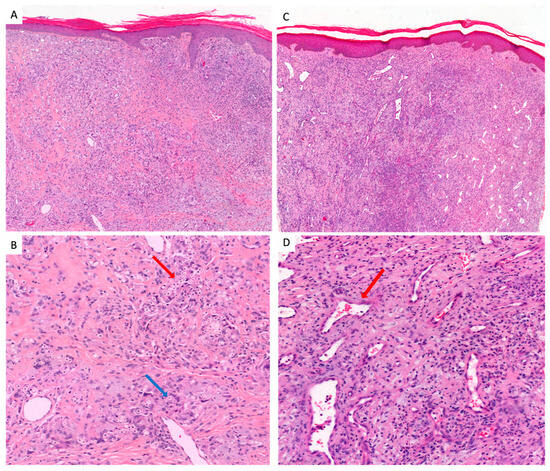

Fungal Density in Lobomycosis in French Guiana: A Proposal for a New Clinico-Histological and Therapeutic Classification

Background: Lobomycosis is a rare cutaneous tropical neglected disease caused by the fungal agent Lacazia loboi, recently renamed Paracoccidioides lobogeorgii. Our objectives were to present all cases of lobomycosis diagnosed in French Guiana, to offer a precise description of their histopathological [...] Read more.

Background: Lobomycosis is a rare cutaneous tropical neglected disease caused by the fungal agent Lacazia loboi, recently renamed Paracoccidioides lobogeorgii. Our objectives were to present all cases of lobomycosis diagnosed in French Guiana, to offer a precise description of their histopathological features and to propose a new clinico-histological prognostic classification. Methods: All cases of lobomycosis diagnosed in French Guiana between 1959 and 2022 were included. We looked for associations between the occurrence of relapses and the clinic-histological form. Results: 31 patients diagnosed with lobomycosis were included. An epidemiological shift was observed in the 2000s as Brazilian patients became the most important ethnic group. Gold mining, forestry and fishing/sailing were reported as professional exposures. New histological features, such as inflammatory “rosettes” formations were described. We describe two clinic-histological patterns: a major form (high fungal density and/or multifocal lesions) and a minor form (low fungal density, unifocal lesions, association with fewer relapses). Conclusions: The changing epidemiology of lobomycosis in French Guiana is characterized by a shift towards Brazilian patients, mostly gold miners. Minor forms should be treated with surgery, major forms with a combination of surgery followed by nultiple drug therapy (MDT) or posaconazole. Full article